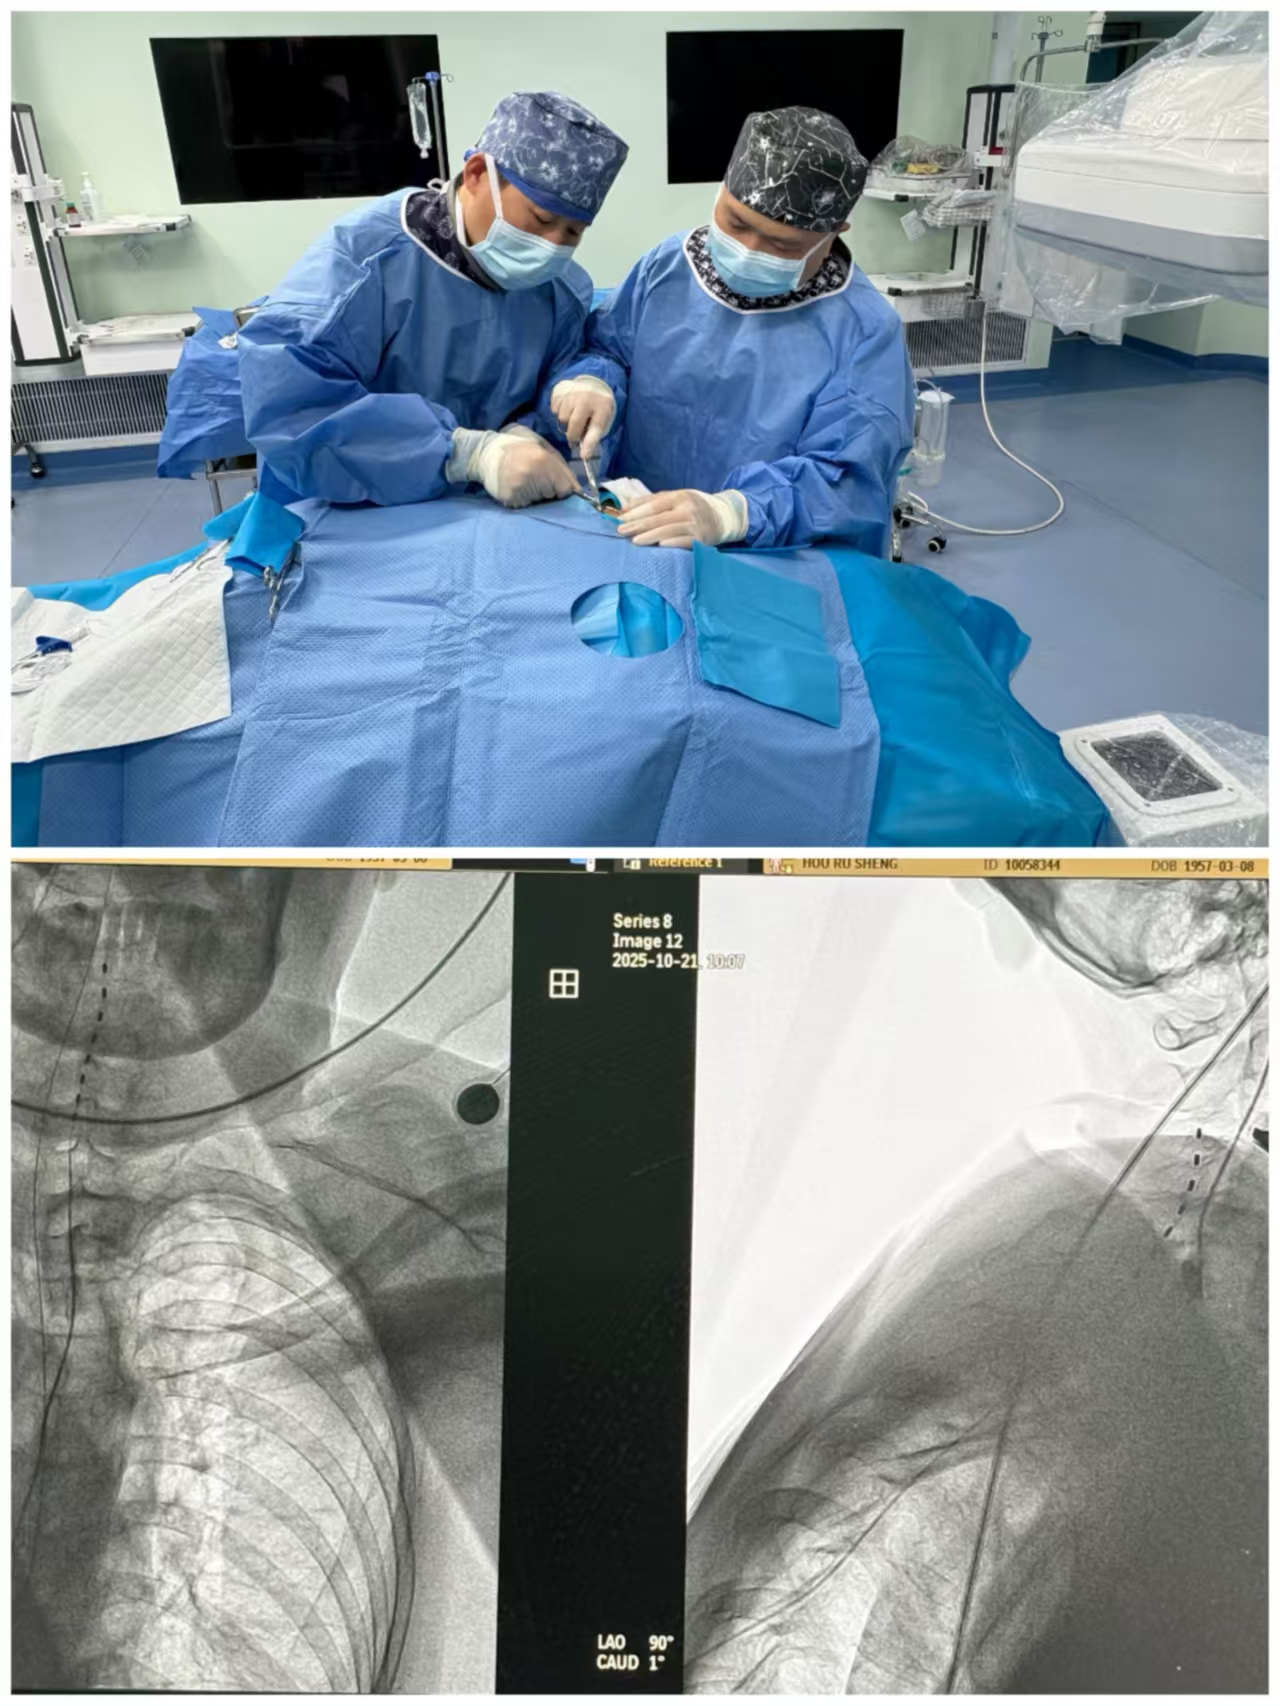

经综合评估,我院神经外科李华龙副主任医师向家属建议可先行植入测试电极进行脊髓电刺激。若治疗效果理想,后期再置入永久性脊髓电刺激器,首先缓解患者肢体疼痛,其次降低肌张力改善肢体运动功能、提高生活质量。首都医科大学附属天坛医院功能神经外科主任张建国教授来院为患者会诊后,患者家属愿意接受手术。2025年10月22日,首都医科大学附属天坛医院功能神经外科徐珑教授和我院李华龙副主任医师在我院导管室、麻醉团队密切协作,顺利完成手术,X线影像确认测试电极位置理想。术后次日开始进行脊髓电刺激治疗,现已测试治疗2周,患者肢体疼痛明显改善,四肢肌张力较前下降,上肢肢体关节活动度有所好转。患者术后恢复良好,拟择期进一步为患者置入永久性脊髓电刺激器。